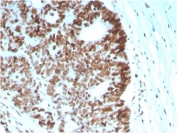

IHC staining of FFPE human lymph node with MSH6 antibody (clone MSH6/2927). HIER: boil tissue sections in pH 9 10mM Tris with 1mM EDTA for 10-20 min and allow to cool before testing.